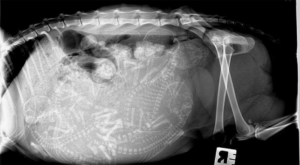

На рентгене хорошо просматриваются кости и позвоночник. Шерсть уже полностью сформирована. В целом на 50-й день котята уже готовы к рождению, но данный момент также зависит от породы.